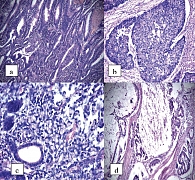

Рис. 2. Гистологическая характеристика множественного синхронного РТК при ЯК (МОНИКИ. Больная Х., 56 лет. Препарат Г.А. Поляковой.

Морфологические варианты РТК при ЯК и БК включают (рис. 2): аденокарциному, слизистый рак, солидный рак, плоскоклеточный рак, недифференцированную форму, скиррозный рак, лимфому.